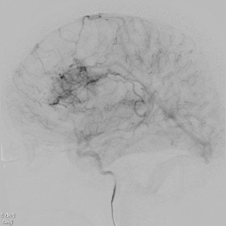

MRI検査 CT検査 血管造影

血管増生の評価や術前に血管の走行を確認するために用いる。